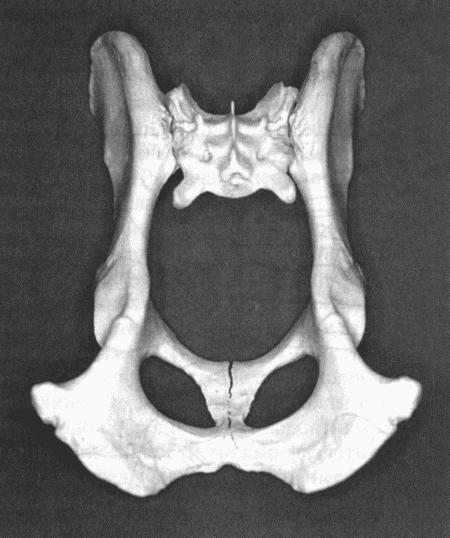

• Узкий тазовый канал — одна из причин дистоции. Патология является результатом перенесенной травмы таза, незрелостью или врожденным недоразвитием таза. В норме вертикальный диаметр таза превышает горизонтальный (фиг. 12.7). Врожденная узость родового канала наблюдается у некоторых брахеоцефальных пород и терьеров, вдобавок отличающихся относительно крупным черепом и плечевым поясом. При наличии ахондроплазии (например, у скотч-терьеров) дорсо-вентральное уплощение приводит к искажению нормального профиля таза и создает обструкцию родовых путей. Чрезмерно широкая грудная клетка при выраженном сужении в пояснице (у бульдогов) приводит к опущению матки во время беременности и смещению родовых путей под острым углом. Кроме того, у бульдогов часто наблюдается вялость брюшной мускулатуры, по этой причине сокращений матки и потуг бывает недостаточно для того, чтобы поднять плоды в полость таза.

Фиг. 12.7.

Нормальный таз собаки. Очевидно, что внутреннее пространство полости имеет овальную форму, и диагональ длиннее поперечного сечения